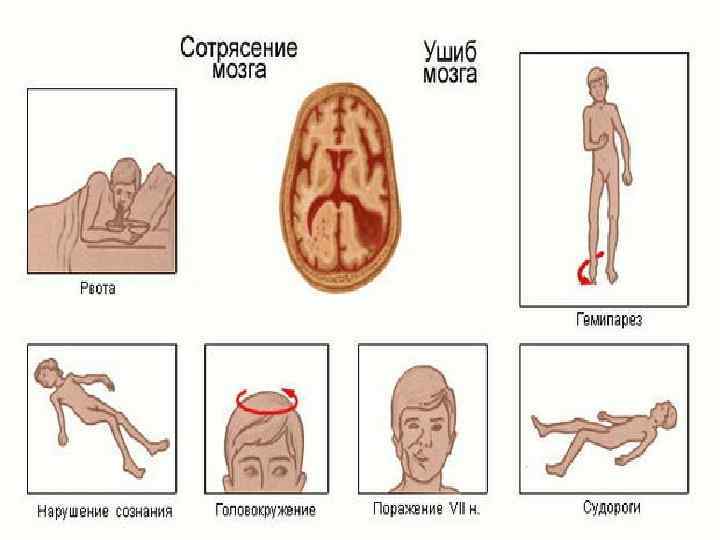

Ми шайқалуы – мидың ең жеңіл зақымдануы. Оның клиникасында міндетті түрде ми құрылымдарының функциясы қалпына келетін, зақымдану дәрежесі өрескел емес бұзылымдар басым. Бірнеше секундтан 10 минутқа дейін созылатын қысқа мерзімді естен тану, лоқсу, құсу, вестибулярлық бас айналу байқалады. Кейіннен қарқыны әр түрлі, 7 -10 минутта басылатын бас ауруы, ретроградтық амнезия пайда болады.

Ми шайқалуының алғашқы сағаттарында анизокория, орталық мимикалық бұлшық еттерінің парезі, сіңір рефлекстерінің асимметриясы түрінде білінетін жеңіл ошақтық неврологиялық симптомдар көрініс беруі мүмкін.

Ми жарақаты Ми жарақаты, ми шайқалуына қарағанда, әр деңгейде білінетін ошақтық неврологиялық симптомдармен сипатталады. Ми жарақатының жеңіл, орта және ауыр дәрежелері ажыратылады. Жеңіл дәрежелі ми жарақаты – бірнеше минуттан бір сағатқа дейін созылатын естен тану. Ес кіргеннен кейін, жалпы милық симптомдармен бірге, брадикардия мен тахикардия, артериялық гипертензия пайда болуы мүмкін.